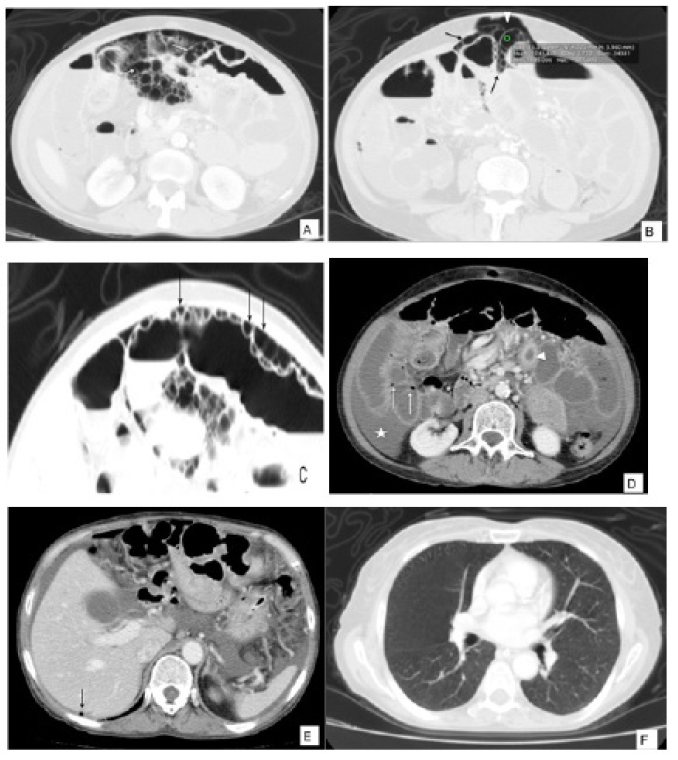

Ante la poca mejoría de los síntomas con el tratamiento médico se solicitó tomografía de abdomen (figura 1) en la que se observaron múltiples imágenes quísticas, redondeadas, localizadas en la pared del intestino delgado asociadas a ligero engrosamiento parietal del yeyuno, neumoperitoneo y líquido libre intra-abdominal. No se visualizaron alteraciones de las estructuras vasculares, pileflebitis ni neumobilia.

Figura 1 a, b. Tomografía computarizada (TC) contrastada de abdomen en ventana de pulmón donde se observan múltiples imágenes redondeadas localizadas en la pared del intestino delgado con densidad de aire (-1041 UH) (flechas blancas). Nótese el neumoperitoneo asociado (Cabeza de flecha) Figura 1 c. Magnificación de las imágenes hipodensas de la pared abdominal (flecha). Figura 1 d, e. TC de abdomen en ventana de tejidos blando donde se observa engrosamiento concéntrico y realce de la pared del yeyuno (cabeza de flecha blanca) además de liquido libre intra-abdominal (asterisco) e imágenes hipodensas en la pared del intestino delgado (flechas blancas). Aire libre en el hipocondrio derecho (flecha negra), no hay defecto de llenado ni aire en la vena porta. Figura 1e. Lo incluido de las bases pulmonares sin alteraciones parenquimatosas.

Teniendo en cuenta los antecedentes y hallazgos imaginológicos ya descritos en un estudio tomográfico previo, se hace el diagnóstico de neumatosis intestinal quística de origen benigno. La paciente tuvo una evolución satisfactoria sin tratamiento, solo con observación y fue dada de alta sin complicaciones.